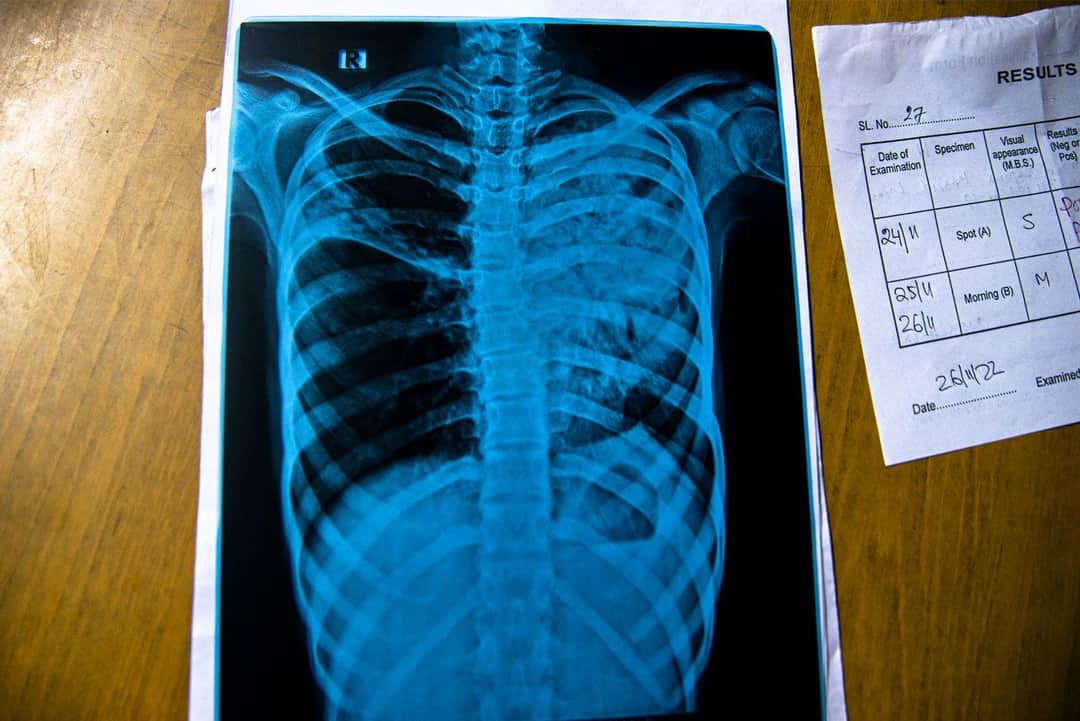

ஜரிகை நூலில் பூத்தையல் போடுவதில் ஜமில் அனுபவம் வாய்ந்தவர். ஹவுரா மாவட்டத்தை சேர்ந்த 27 வயது தொழிலாளரான அவர், கால்களை மடித்து தரையில் பல மணி நேரங்கள் அமர்ந்து கொண்டு, விலையுயர்ந்த துணிகளுக்கு பொலிவை கூட்டி ஜொலிக்க வைக்கிறார். இருபது வயதுகளில் எலும்பு காசநோய் வந்த பிறகு, ஊசியையும் நூலையும் தூர வைக்க வேண்டி வந்தது. நோயால் அவரின் எலும்புகள் பலவீனமாகின. நீண்ட நேரங்களுக்கு கால்களை மடக்கியிருக்க முடியாமல் அவருக்கு போனது.

அதே மாவட்டத்தில் ஆவிக் மற்றும் அவரது குடும்பம் கவுராவின் பில்கானா குப்பத்தில் வாழ்கின்றனர். பதின்வயதில் இருக்கும் அவருக்கும் எலும்பு காசநோய் இருக்கிறது. 2022ம் ஆண்டின் நடுவே அவர் பள்ளிப்படிப்பை நிறுத்த வேண்டியிருந்தது. ஓரளவுக்கு அவர் தேறிக் கொண்டிருந்தாலும், பள்ளிக்கு மீண்டும் செல்ல முடியவில்லை.